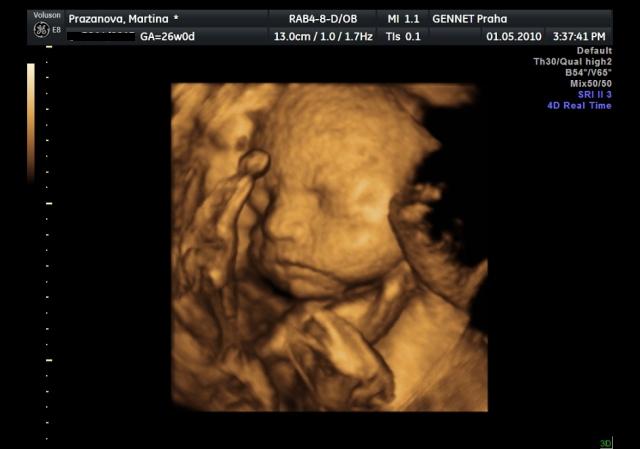

Už se nemůžeme dočkat 1.5....jdeme na 4D UTZ, tak doufám, že se nám ten náš klučík ukáže v plné své kráse 🙂))